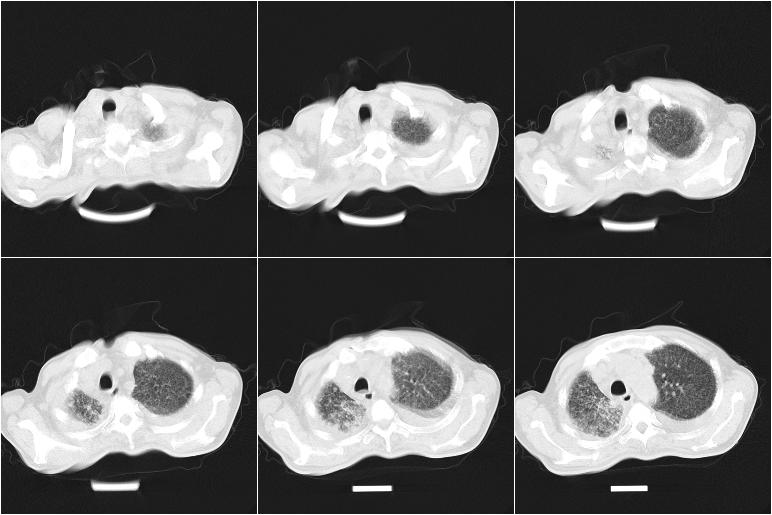

以下是引用边生丽在2009-8-17 11:43:00的发言:[br][br] [br] 右肺中心型癌伴右肺下叶不张、双肺转移并癌性淋巴管炎、心包和双侧胸腔积淮(转移?)、脑转移、肝转移、多骨(颅骨、椎骨)转移。 [br] [br]

以下是引用奥特之父在2009-4-20 19:58:00的发言:[br]支持胰腺癌并转移性病变。

以下是引用随光逐影在2009-8-17 14:09:00的发言:[br]支持 右肺中央型癌伴右肺下叶肺不张,纵隔淋巴结转移,双肺转移并癌性淋巴管炎,心包和双侧胸腔积液,脑转移、肝转移、多发性骨(颅骨、脊椎)转移。